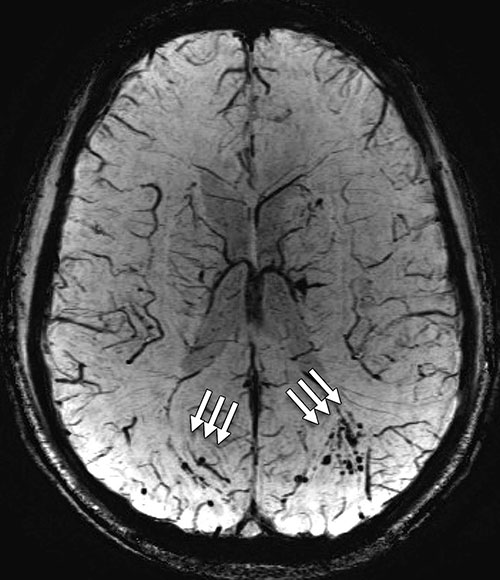

The participants were diagnosed with predominantly chronic (mean, 1,381 days; median, 888 days after injury) and mild (92 percent [768 of 834]) TBI. Of these participants, 84.2 percent (688 of 817) reported one or more blast-related incident and 63.0 percent (515 of 817) reported loss of consciousness at the time of injury. The presence of white matter T2-weighted hyper-intense areas was the most common pathologic finding, observed in 51.8 percent (432 of 834; OR, 1.75) of TBI participants. Cerebral microhemorrhages were observed in a small percentage of participants (7.2 percent [60 of 834]; OR, 6.64) and showed increased incidence with TBI severity (P < .001, moderate and severe vs. mild). T2-weighted hyper-intense areas and microhemorrhages did not collocate by visual inspection. Pituitary abnormalities were identified in a large proportion (29.0 percent [242 of 834]; OR, 16.8) of TBI participants.